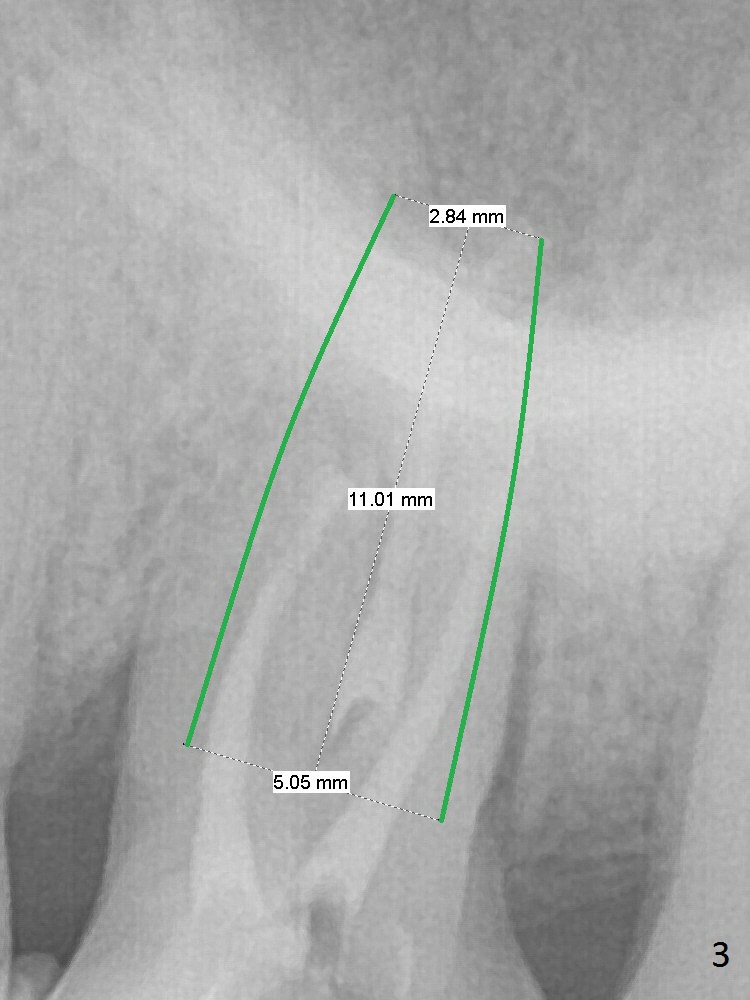

A 70-year-old woman has pain at MB root area post RCT at #14 (Fig.1,2). The tooth seems to have endo-perio disease (bone loss with gingival recession at MB) and be non-salvageable. After extraction and Metronidazole treatment, start osteotomy with 1.6 mm drill 1-2 mm shy of the sinus floor, followed by PA. Use Lindamann bur for ostetoomy position and trajectory adjustment. Use Marking Bur if necessary before Magic Drill 4.3 mm if the septum is wide. The depth of the osteotomy is 1-2 mm coronal to the sinus floor. Do not use the final drill, i.e., saving the osteotomy plug in place. Next 4.5x11 mm dummy implant is placed to push the plug upward for lifting. Place an implant as large as possible, but not violating the buccal gap (Fig.3).